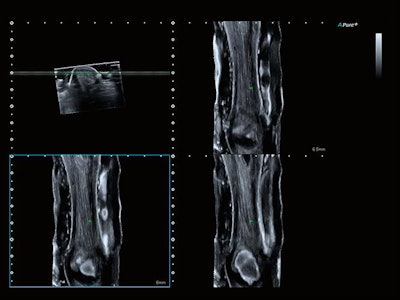

The company's Aplio i800 now features a 33-MHz linear-array transducer that is designed to offer better spatial resolution below 50 microns and improved resolution and detail for B-mode and color flow imaging. Its Smart Sensor 3D allows users to take 3D volumes with a standard linear or convex transducer. The system is particularly suitable for superficial subcutaneous imaging and examinations of small joints and superficial nerves, as well as for superficial vascular evaluations.

Image of Achilles tendon. Coronal view acquired on the Aplio i800 system with Smart 3D at 24 MHz. Image courtesy of Canon.